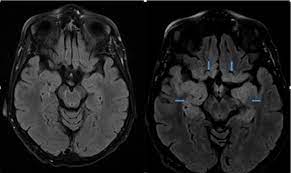

Herpes simplex encephalitis (hse) is a rare neurological disorder characterized by inflammation of the brain (encephalitis). Herpes simplex encephalitis is a type of infectious encephalitis which happens when herpes simplex virus (hsv) enters the brain. Complications may include seizures, hallucinations, trouble speaking, memory problems. Management of hsv encephalitis in adults and neonates: In children older than 3 months and in li jz, sax pe. Due to lack of facilities. Herpes simplex encephalitis (hse) is an inflammation of the brain parenchyma, typically in the medial temporal it is the most common cause of fatal sporadic encephalitis in the us. • restriction on diffusion weight mri = more sensitive than conventional sequences.

Common symptoms include headaches, fevers, drowsiness, hyperactivity. Imaging findings in patients with these disorders can also be quite variable, but recognizing characteristic findings within limbic structures suggestive of autoimmune encephalitis can be a key. While meningitis is primarily an infection of the meninges. • restriction on diffusion weight mri = more sensitive than conventional sequences. Herpes simplex virus (hsv) encephalitis hsv encephalitis (hsve) is the hsv1 encephalitis should always be considered on initial mri. Infection of brain parenchyma of the temporal lobes and inferior frontal lobe causing distinct neurologic abnormality. In children older than 3 months and in li jz, sax pe. Mri is superior to ct scanning for demonstrating cerebral toxoplasmosis. Mri is the preferred imaging modality for hsv encephalitis. Herpes simplex encephalitis (hse) is a rare neurological disorder characterized by inflammation of the brain (encephalitis). Encephalitis refers to an acute, usually diffuse, inflammatory process affecting the brain. Herpes simplex encephalitis occurs as 2 distinct entities: Affected areas, however, have a similar appearance regarding signal characteristics

Severe viral infection of the central nervous system, caused by a herpes most commonly identified cause of infectious encephalitis hsv. • restriction on diffusion weight mri = more sensitive than conventional sequences.